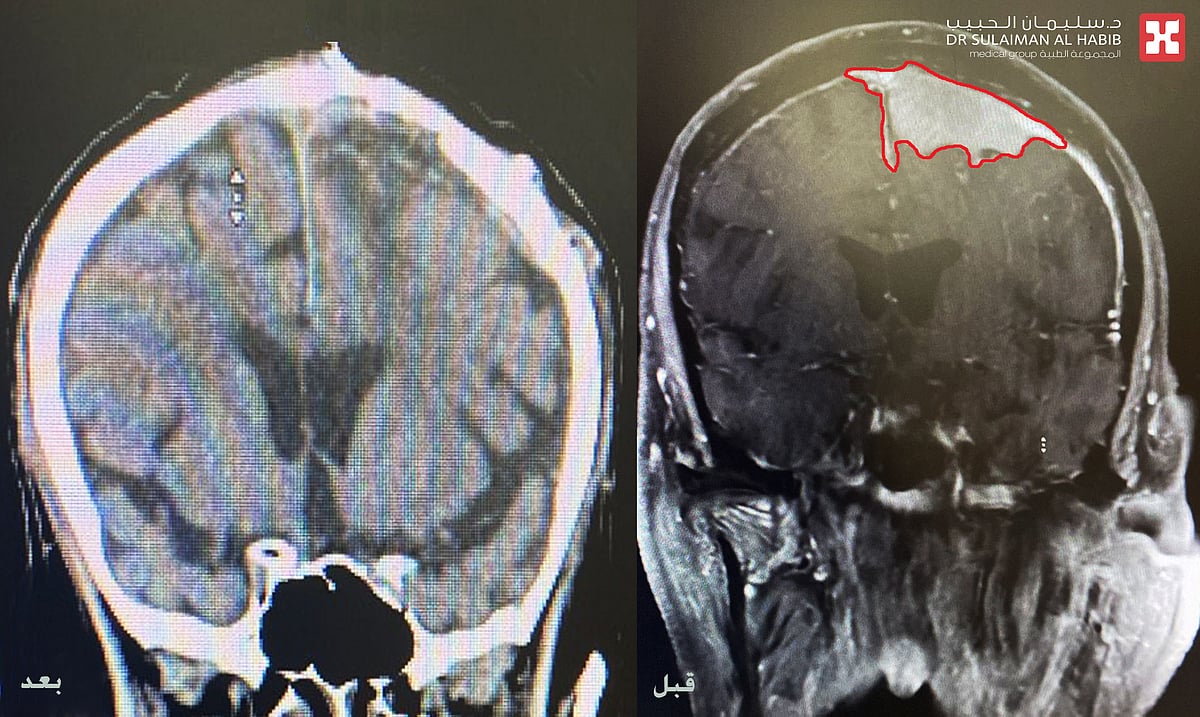

مجمع الدكتور سليمان الحبيب بالعليا يستأصل ورماً دماغياً كبيراً سبب صداع مزمن وتشنجات حادة لمراجع سبعيني

تمكن مجمع الدكتور سليمان الحبيب الطبي بالعليا، من إجراء عملية جراحية دقيقة ومعقدة، لإستئصال ورم كبير بالدماغ، وذلك لإنهاء معاناة مراجع يبلغ من العمر 72 عاماً، كان يشكو من إصابته بحالة من النوبات التشنجية الحادة والمتكررة في كامل الجسم مع الشعور بالصداع، الأمر الذي أفقده القدرة على أداء مهامه اليومية. ذكر ذلك الدكتور هاني عبد العزيز استشاري جراحة المخ والأعصاب رئيس الفريق الطبي المعالج، الحاصل على الزمالة الكندية.